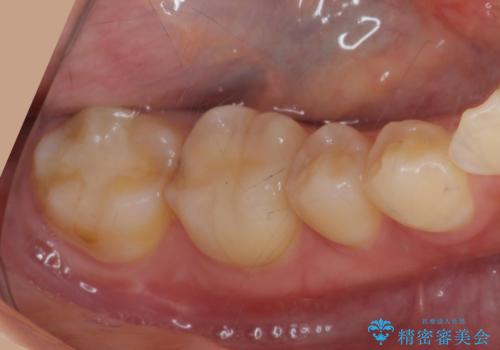

銀歯が取れた 中が虫歯 セラミックインレーに

- 矯正治療中に銀の詰め物が取れたとのことでした。

中が虫歯になっていたため、虫歯を除去し、セラミックインレーにやり変えました。

- emax プレスインレー 7万円費用は治療当時の料金となります

詰め物が取れてくる場合は、中が虫歯で取れる場合があります。

その際は元の詰め物をつけることはできず、インレーのやりかえとなります。